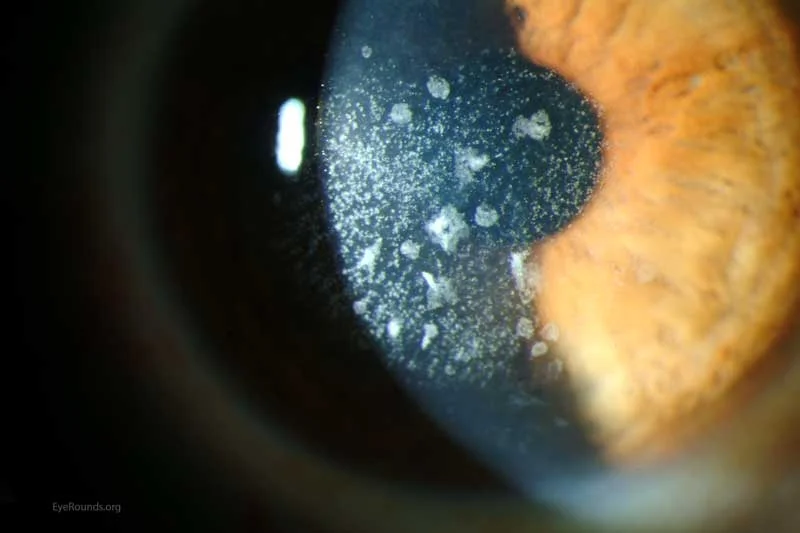

쉽게 설명해 드릴게요. 우리 눈의 검은자(각막)는 유리창처럼 투명하고 깨끗해야 사물이 선명하게 보입니다. 그런데 이 각막에 흰 점들이 생기고, 시간이 지날수록 그 점들이 점점 많아지고 넓어지는 병입니다.

우리가 쓰는 안경 렌즈를 생각해보세요. 렌즈가 깨끗해야 잘 보일 텐데, 렌즈 표면에 하얗게 스크래치(기스)가 가득하다면? 아무리 도수가 맞아도 앞이 뿌옇게 보이겠죠. 아벨리노 각막 이영양증은 바로 그런 상태가 우리 눈의 검은자(각막)에서 진행되는 유전 질환입니다.

위의 사진처럼 각막에 흰색 혼탁(점)들이 생긴 것이 보이시나요? 이것들이 모두 아벨리노 각막 이영양증의 증상이며, 사람마다 매우 다양한 형태로 나타납니다.